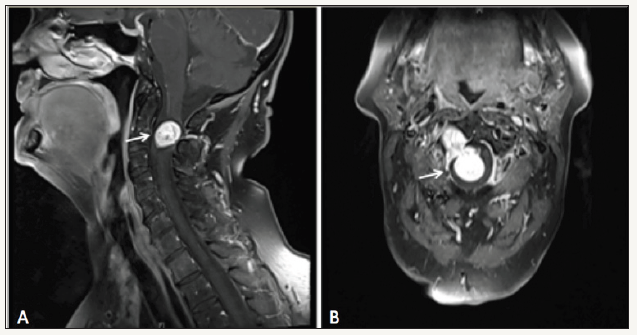

Figure 1: Preoperative contrast MRI of the cervical spine A- sagittal view, B- coronal view showing typical intra-extradural and dumbbell-shaped mass at the level of C2-C3 vertebrae.

The MRI revealed a 15 x 30 mm contrast-enhanced mass located at the level of C2-C3 vertebrae (Figure 1). The lesion caused a severe displacement of the cord to the left side. The CT with CTangiography revealed the expanded neuroforamen C2/3 on the right side and the shift of the vertebral artery (VA) Figure 2.